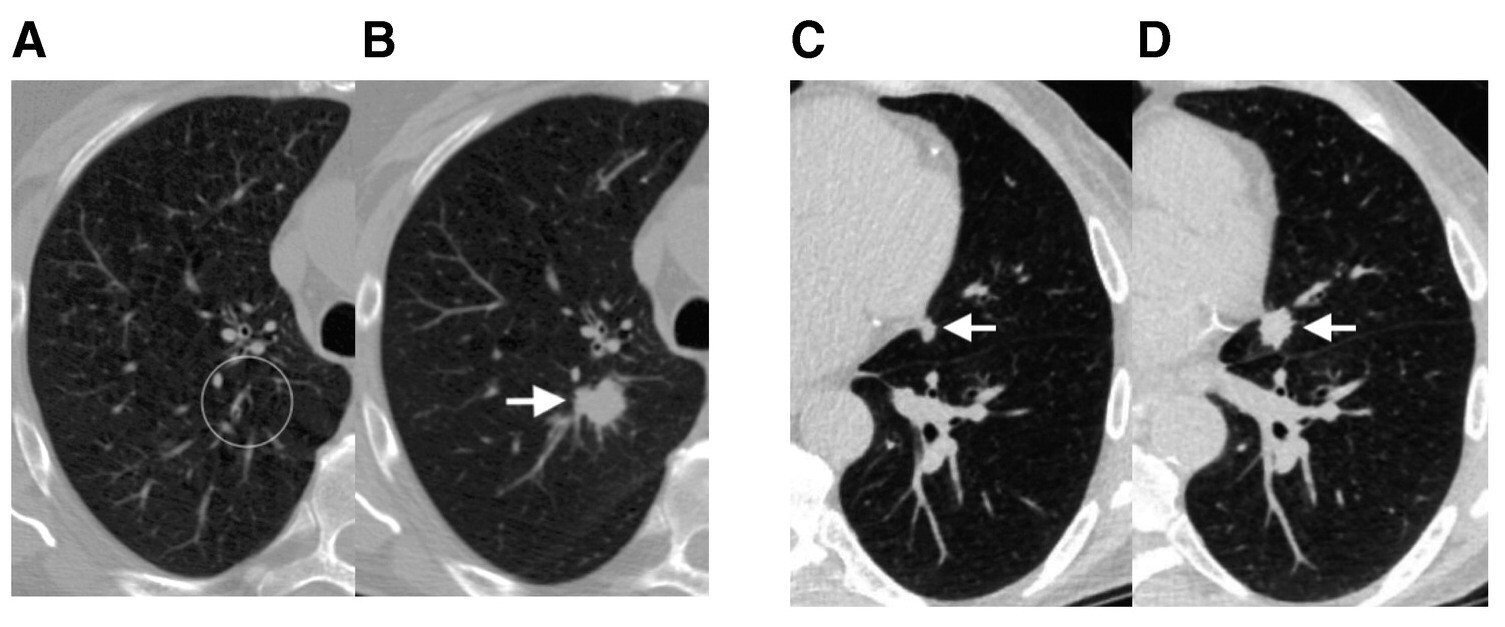

Для предсказания риска развития рака легкого алгоритму достаточно одного снимка низкодозной КТ. В трехмерных изображениях Sybil ищет признаки аномального роста, подозрительные образования, которые определяются по незаметным невооруженному глазу различиям в контрастности областей изображения (Рис. 1). На основе этого алгоритм может делать прогноз относительно вероятности развития рака в ближайшие 1-6 лет.

Рисунок 1. А. Изображение низкодозной КТ легкого пациента (69 лет, история курения 99 пачек в год) без видимых узловых образований в правой верхней доле легкого. Кругом отмечена область, определенная нейросетью как подозрительный участок. B. Изображение низкодозной КТ легкого этого же пациента два года спустя. На снимке определяется плотное узловое образование. По данным резекции был подтвержден низкодифференцированный плоскоклеточный рак легкого размером 2.2 см (pT1cN0M0, стадия IA3). С. Изображение низкодозной КТ легкого пациента (67 лет) с анамнезом курения 30 пачек в год и плотным узловым образованием диаметром 7 мм в язычке легкого рядом с сердцем (стрелка), которое было пропущено радиологом. D. Изображение низкодозной КТ легкого этого же пациента спустя год. Анализ образования размером 1.5 см (указано стрелкой) и образцов тканей средостения подтвердили аденокарциному (cT1bN2M0, стадия IIIA). Источник: Journal of Clinical Oncology, 2023. DOI: 10.1200/JCO.22.01345